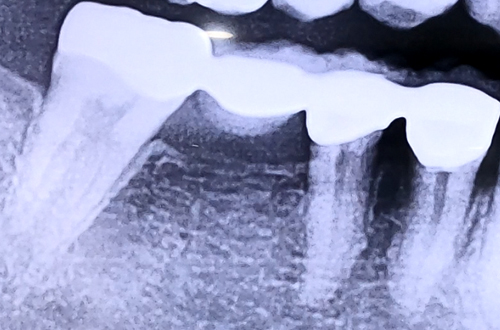

AFTER

브릿지가 가진 특징 때문에 생기는 증상이므로, 브릿지를 제거한 뒤 치아 한 개씩 정상적인 힘만 받도록 개별적으로 치아를 씌워드리고 이가 없는 자리에는 임플란트를 식립하여 치료해 드렸습니다.

브릿지 치료는 최근 임플란트의 활발한 보급과 더불어 잘 진행되지 않습니다만, 임플란트를 하기에 부적절한 잇몸이나 치아 상태에서는 더 나은 결과를 얻기도 하는 등 각각 장단점이 있으므로, 케이스에 따라 임플란트와 브릿지를 선택적으로 진료하는 것이 중요하겠습니다.